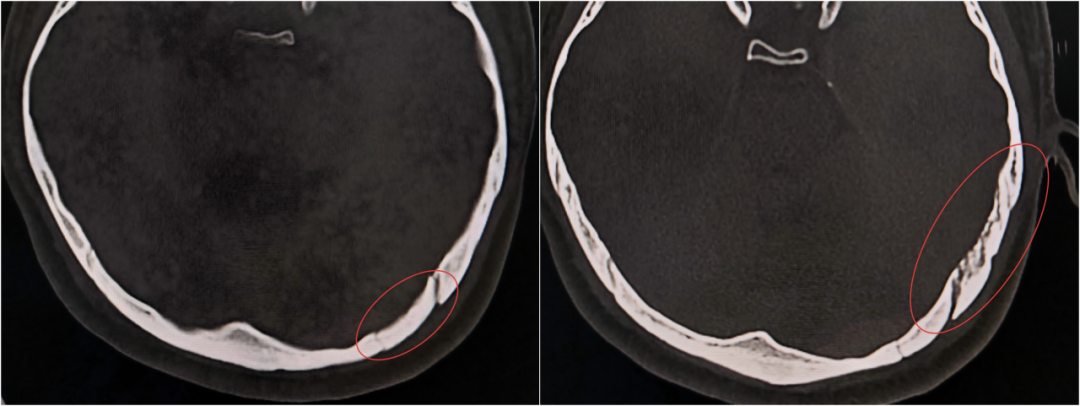

小徐颅脑内部存在多处出血点,枕骨破裂

争分夺秒,必须环环紧扣。完成必要指标监测后,立即将小徐送往放射科,10分钟内完成急诊CT检查。结果显示:枕骨破裂,蛛网膜下腔出血。